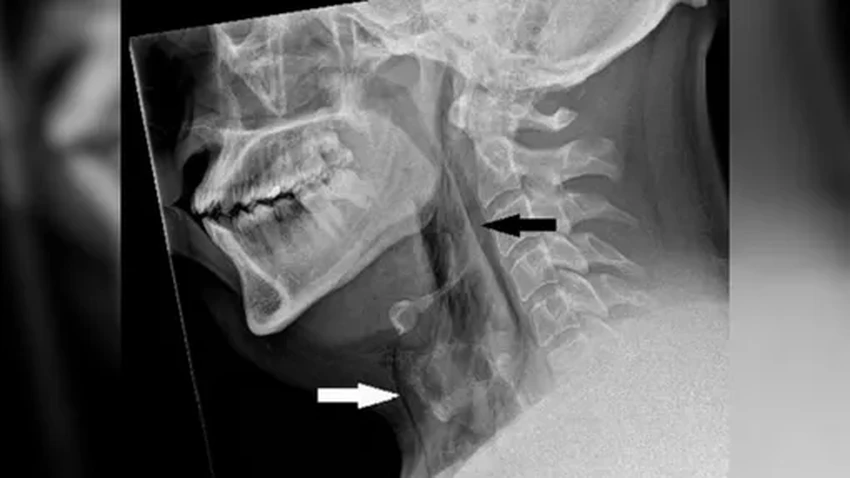

Рентген показал хирургическую эмфизему — воздух проник глубоко под кожу в те ткани, где ему быть совсем не положено. А компьютерная томография выявила крошечную, но опасную дырочку в трахее: 2 на 2 миллиметра в ширину и 5 миллиметров в глубину.